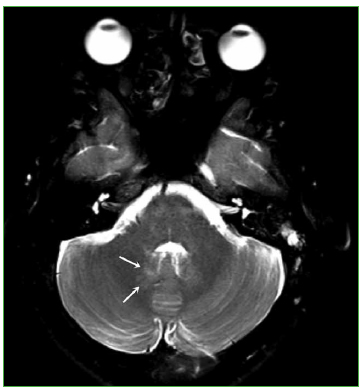

La RM de cerebro reveló anomalías menores en la fosa posterior (Figura 9), sin alteraciones evidentes en el compartimento supratentorial (lo que coincide con los escasos síntomas neurológicos de esta paciente). La RM de columna fue normal.

Figura 9.

Resonancia magnética, corte axial potenciado en T2 con supresión grasa (5470/95) de cerebro. Se reconoce una sutil alteración de señal en la topografía del núcleo dentado derecho (flechas).